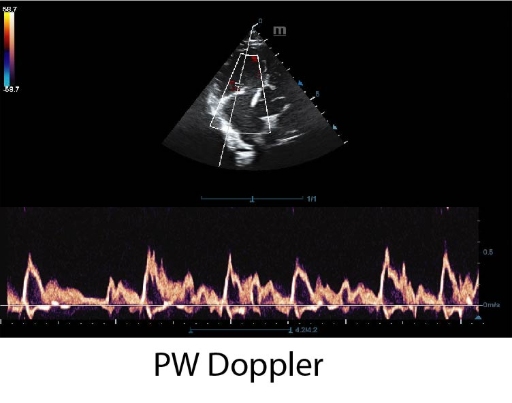

Оборудван с PW доплер, Smart 3D и софтуери с автоматични измервания, DP-50 Vet надминава очакванията на всеки потребител. Компакният нов корпус, повишена мобилност и удобство при работа, правят модела подходящ за множество ветеринарни клинични нужди.